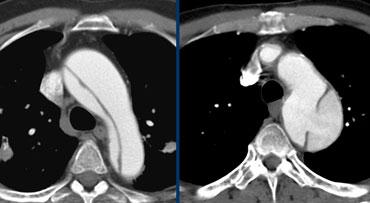

TRÁI: Bóc tách Type A với vạt nội mạc rõ ràng thấy trong quai động mạch chủ. PHẢI: Bóc tách Type B. Điểm vào phía xa động mạch dưới đòn trái.

Các quyết định xử trí dựa trên các thông tin sau:

- Type A hay Type B

- Vị trí điểm vào & điểm ra

- Các nhánh bên liên quan, xuất phát từ lòng thật / lòng giả

- Các cơ quan có nguy cơ (1/3 tỷ lệ tử vong do suy tạng)

- Biến chứng (vỡ, tắc động mạch vành, hở van động mạch chủ, thần kinh)

- Đường kính của lòng thật và lòng giả tại: vùng hạ cánh gần và xa, tại điểm vào và tại vị trí hẹp nhất

- Độ xoắn vặn của mạch chậu